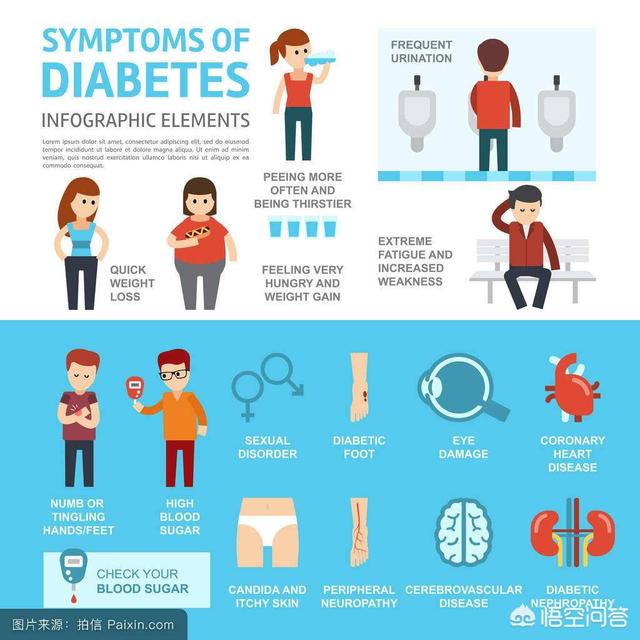

Le principal symptôme du diabète est le fameux "trois de plus et un de moins".Les "trois de plus" sont le fait de manger plus, de boire plus et d'uriner plus ; et le "un de moins" est la perte de poids ou le dépérissement. La raison pour laquelle ces symptômes apparaissent a beaucoup à voir avec les causes du diabète. Le principal indicateur du diabète est une glycémie élevée, supérieure à la normale, et la principale raison en est que les diabétiques ont un métabolisme du glucose anormal, qu'il s'agisse d'un diabète de type 1 ou de type 2, c'est un métabolisme du glucose anormal qui produit le résultat d'une glycémie élevée, ainsi que les symptômes des "trois de plus et un de moins".

1, un appétit inhabituel, manger rapidement et avoir faim, mais perdre de plus en plus de poids. En fait, il s'agit des symptômes typiques du diabète : "trois de plus et un de moins", c'est-à-dire boire plus, uriner plus, manger plus et peser moins.

2. une perte soudaine de la vision, entraînant une vision particulièrement floue. Les premiers stades du diabète sont réversibles car le glucose s'accumule dans l'œil, ce qui entraîne souvent un changement de forme et empêche l'œil de faire la mise au point. Cette maladie doit être distinguée de la rétinopathie diabétique.

3. l'engourdissement et la rigidité des mains et des pieds, souvent accompagnés de douleurs. Les diabétiques ressentent régulièrement un engourdissement et une froideur au niveau des mains et des pieds. Par conséquent, lorsqu'une partie du corps est engourdie et gonflée, en particulier chez les personnes âgées, elle doit être vérifiée rapidement.

4, souvent somnolent, comment dormir pendant la journée n'est pas suffisant, ce qui entraîne une transe mentale. Les heures de somnolence diurne des patients diabétiques sont deux fois plus nombreuses que celles des personnes normales. Cette situation est plus typique chez les personnes âgées diabétiques, car le cerveau est plus sensible à l'oxygène, un manque prolongé d'oxygène provoque des bâillements, suivis d'un manque de concentration, ce qui conduit à l'envie de s'assoupir.

5, le diabète peut entraîner des troubles endocriniens chez l'homme, une diminution de la fonction immunitaire, une diminution de la résistance de la peau, un affaiblissement de la capacité d'autoguérison, une tendance à la récurrence des problèmes de peau, et des niveaux élevés de sucre dans les voies urinaires et le vagin qui constituent un terrain propice aux infections bactériennes pathogènes.

Le diabète sucré se manifeste principalement par une polyurie, une polydipsie, une polyphagie et une perte de poids.

Symptômes courants :Le patient présente une léthargie, une perte de force et une irritabilité. En outre, les démangeaisons corporelles peuvent se manifester par une déficience visuelle, souvent accompagnée d'un engourdissement et d'une sensation de picotement dans les mains et les pieds, et peuvent se compliquer d'ulcères au niveau des pieds. Les femmes peuvent présenter des troubles tels que la ménorragie et l'aménorrhée, tandis que les hommes sont le plus souvent touchés par l'impuissance et la perte de libido.

Les principales manifestations cliniques du diabète sucré sont la polyurie, la polydipsie, la polyphagie, la perte de force et de poids (communément appelée "trois de plus et un de moins"), l'hypoglycémie préprandiale, les démangeaisons cutanées, la susceptibilité aux infections cutanées, la perte de vision et les complications chroniques du diabète sucré telles que l'engourdissement des mains et des pieds, les crises de panique et l'essoufflement, la diarrhée et la constipation, la rétention urinaire et les troubles de l'érection ("l'impuissance"). impuissance) et d'autres manifestations des complications chroniques du diabète.